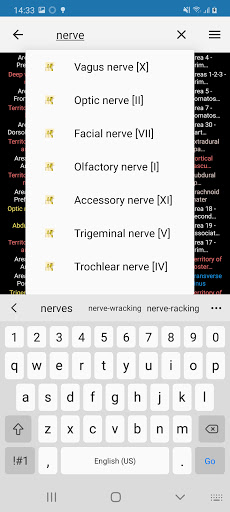

- Localice fácilmente las estructuras anatómicas gracias a la búsqueda de índice

*Encuentre sus partes anatómicas más fácilmente gracias a la nueva función de búsqueda, más intuitiva y poderosa.